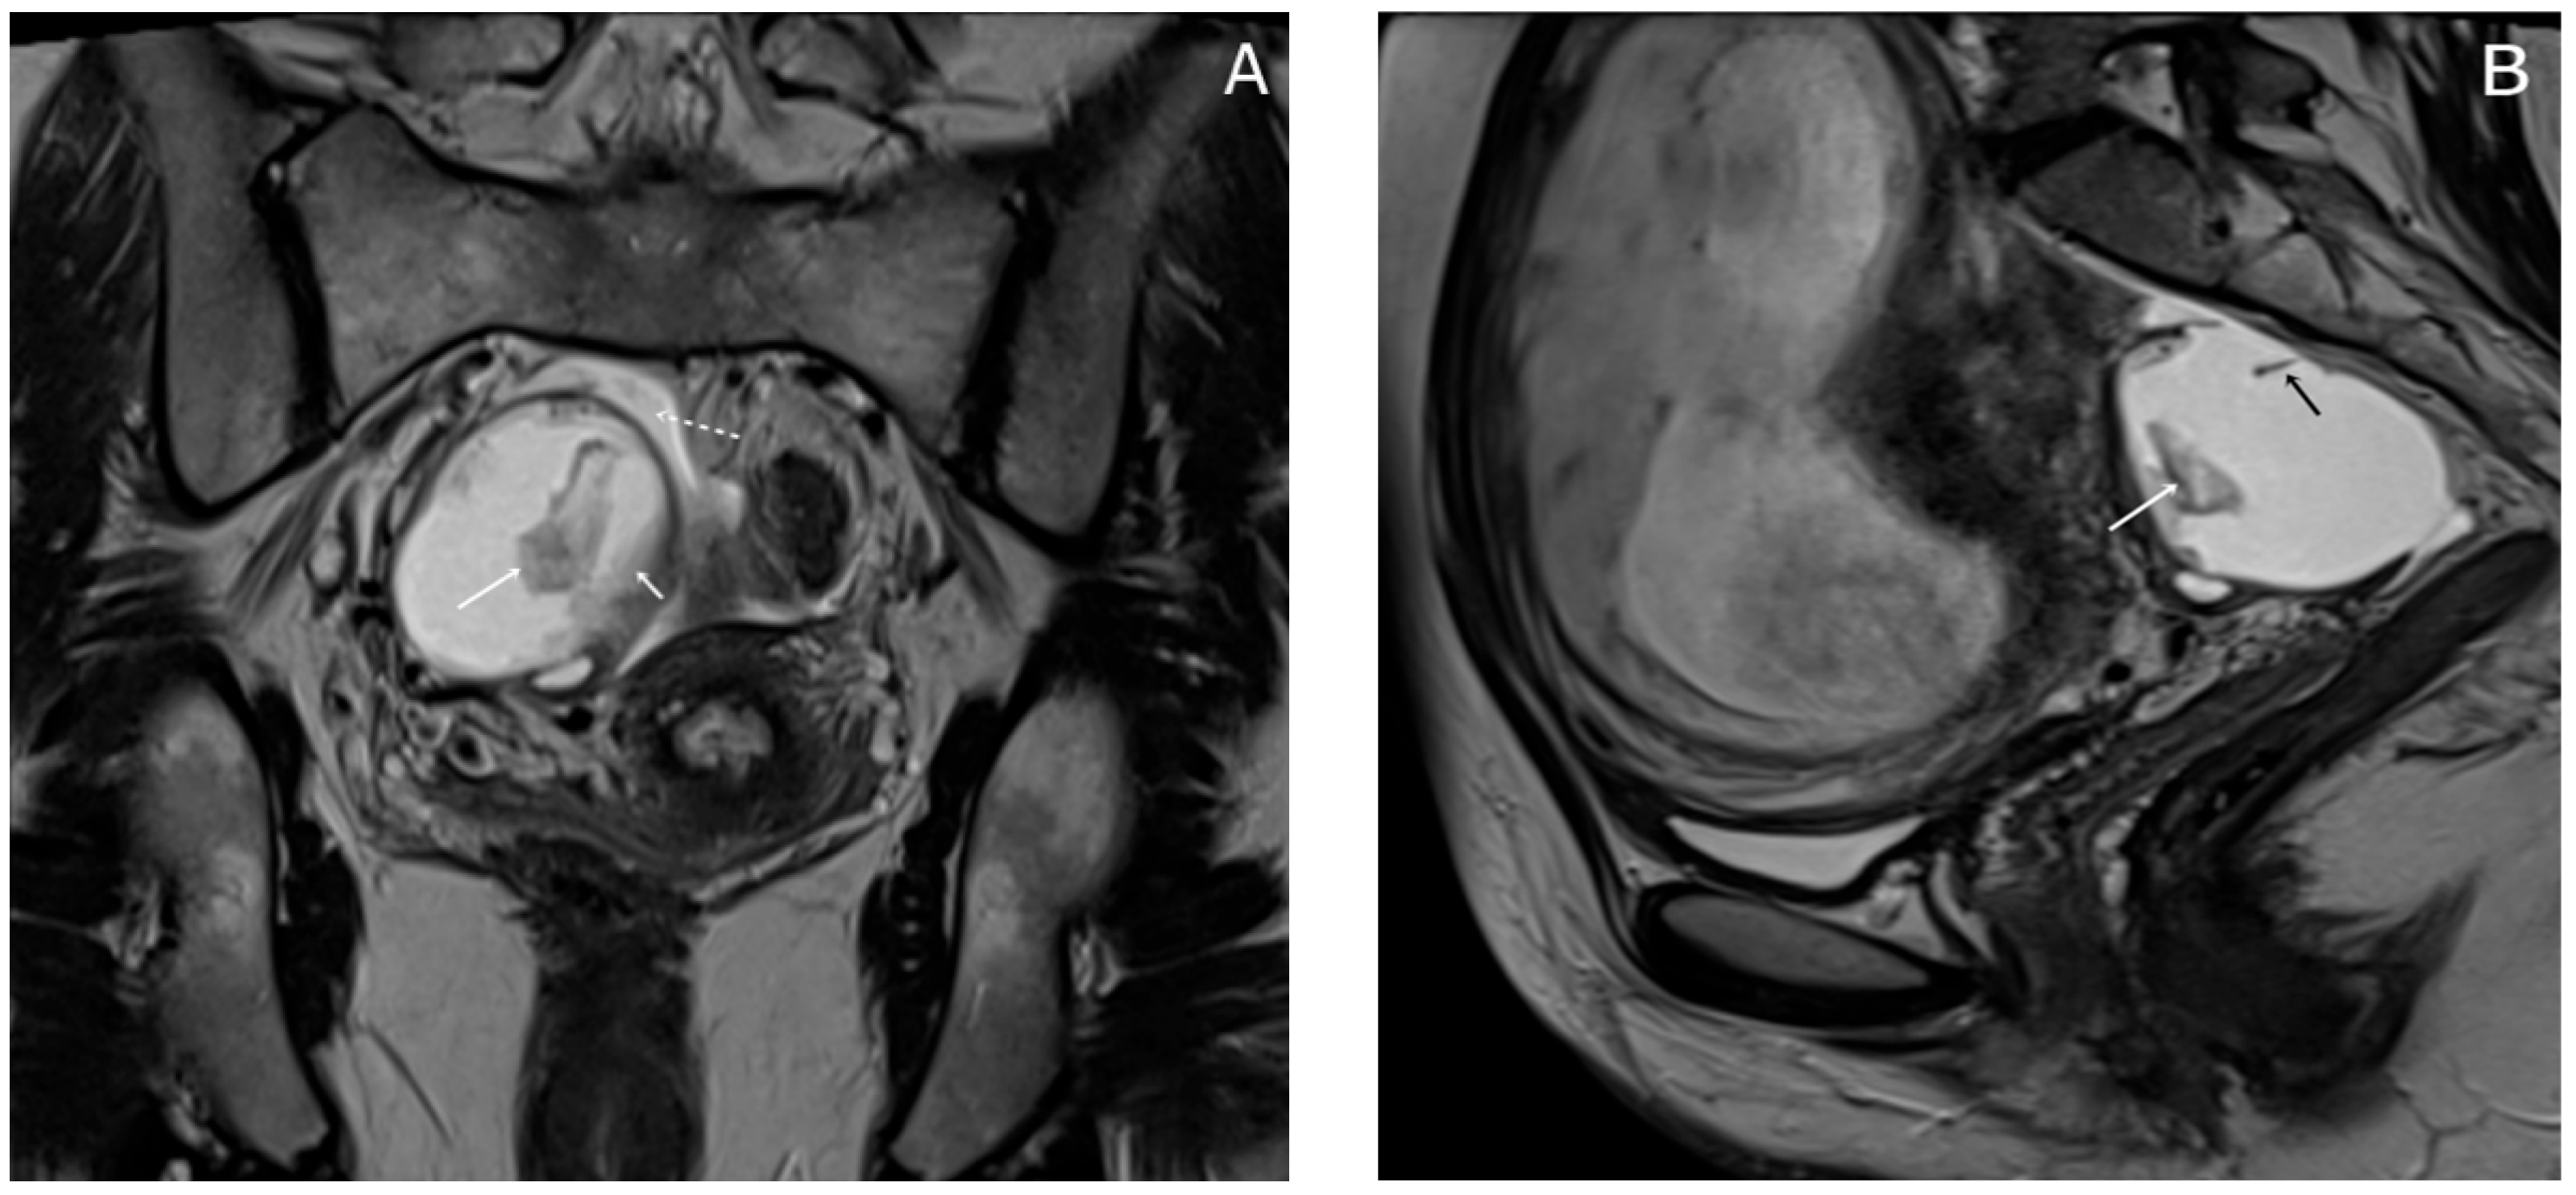

Almost a week later she performed a native MRI which highlighted: uterus with cranio-caudal dimensions of approximately 17 cm, no suspicious lesions at the level of the fetal content are visualized on the sequences performed; the left ovary measures approximately 37 mm in the anteroposterior plane; a space-replacing cystic process (ORADS4), located at the level of the right ovary, extended over an area of up to 56/45/60 mm (ap/ll/cc), reveals filiform septation of up to 2 mm in the right anterolateral quadrant, inhomogeneous solid inclusions with a thickness of up to 9 mm, approximately 3 papillary projections, intralesional hemorrhagic stigmata and a wall with a thickness of up to 3 mm; no space-replacing processes evident on MRI at the level of the rectal wall; no bone lesions with an oncological meaning evident in the examined MRI field; infracentimetric lymph nodes in the short axis located at the level of the internal and external iliac stations bilaterally (Figure 4, Figure 5 and Figure 6).

Figure 5. Axial T1WI-TSE image (A) and axial T2WI-TSE image (B) show a unilocular right ovarian cystic mass. The signal intensity of the cystic component demonstrates intermediate signal on T1WI and high signal on T2WI. The intracystic papillary projection appears hyperintense on T1WI and hypointense on T2WI (arrows).

Figure 6. Axial DWI b800 s/mm2 image. (A) hyperintensity of the papillary projection of the endometrioma (arrow); apparent diffusion coefficient (ADC) map axial image. (B) low signal intensity of the papillary projection (arrow); these findings show restricted diffusion of the papillary projection; the cystic component shows no restricted diffusion.